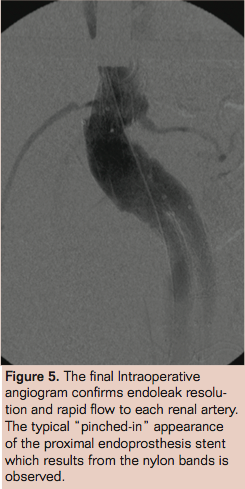

In the operating theatre under local anesthetic infiltration (20 mL Lignocaine 1%) and intravenous sedation (5 mg Midazolam), percutaneous puncture of both common femoral arteries was followed by the insertion of 8 Fr bright tip sheaths (Cordis) followed by two Perclose Proglide suture mediated closure devices (Abbott Vascular) in each vessel using the “preclose” technique.9 Diagnostic angiography demonstrated the location of the rupture, as well as challenging neck anatomy (as described) and diseased iliac access vessels (Figure 2).

Periaortic banding is a technique that has been described in the elective treatment of type 1A endoleak.17-19 It involves a limited laparotomy and careful dissection around the aorta immediately below the renal arteries. In the rupture setting, care must be taken to avoid any retroperitoneal hematoma so as not to exacerbate bleeding. A large right-angle clamp can be passed around the aortic neck taking care to avoid injury to adjacent structures, particularly the renal arteries, veins, and lumbar vessels. Once around the aorta nylon tapes can be tied to snug and seal the aortic wall against the stent graft. Care must be taken to avoid over tightening which may result in stent-graft collapse and involution. The length of aortic neck will determine how many tapes can be accommodated. Normally the placement of 2 to 3 is possible and sufficient to provide a seal. The femoral access sheaths are left in place and final angiography performed to confirm flow through the aortic graft, renal arteries, and the resolution of endoleak (Figure 5). If there is suspicion of bowel ischemia or compartment syndrome, the abdominal cavity may be left open to facilitate a second look laparotomy as well as decompress.